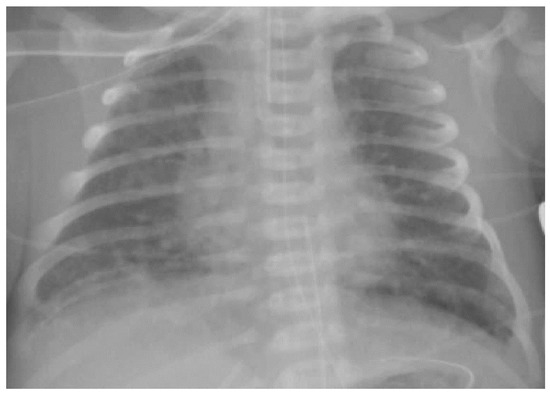

The diagnosis of MAS is based on maternal history (full-term or post-term pregnancy, perinatal distress, the presence of MSAF), clinical features (a full-term or post-term newborn with meconium painted skin and respiratory distress characterized by the hyperexpansion of the thorax) and a chest X-ray (pulmonary hyperinflation with cottony and patchy infiltrates alternating with areas of hypertransparency; Figure 2).

Of note, the severity of the radiological picture does not always correlate with the clinical severity [4] thus suggesting that the severity of MAS is due to other factors (such as pulmonary hypertension) beyond the degree of airway obstruction and parenchymal damage.

Figure 2. Chest X-ray of meconium aspiration syndrome.